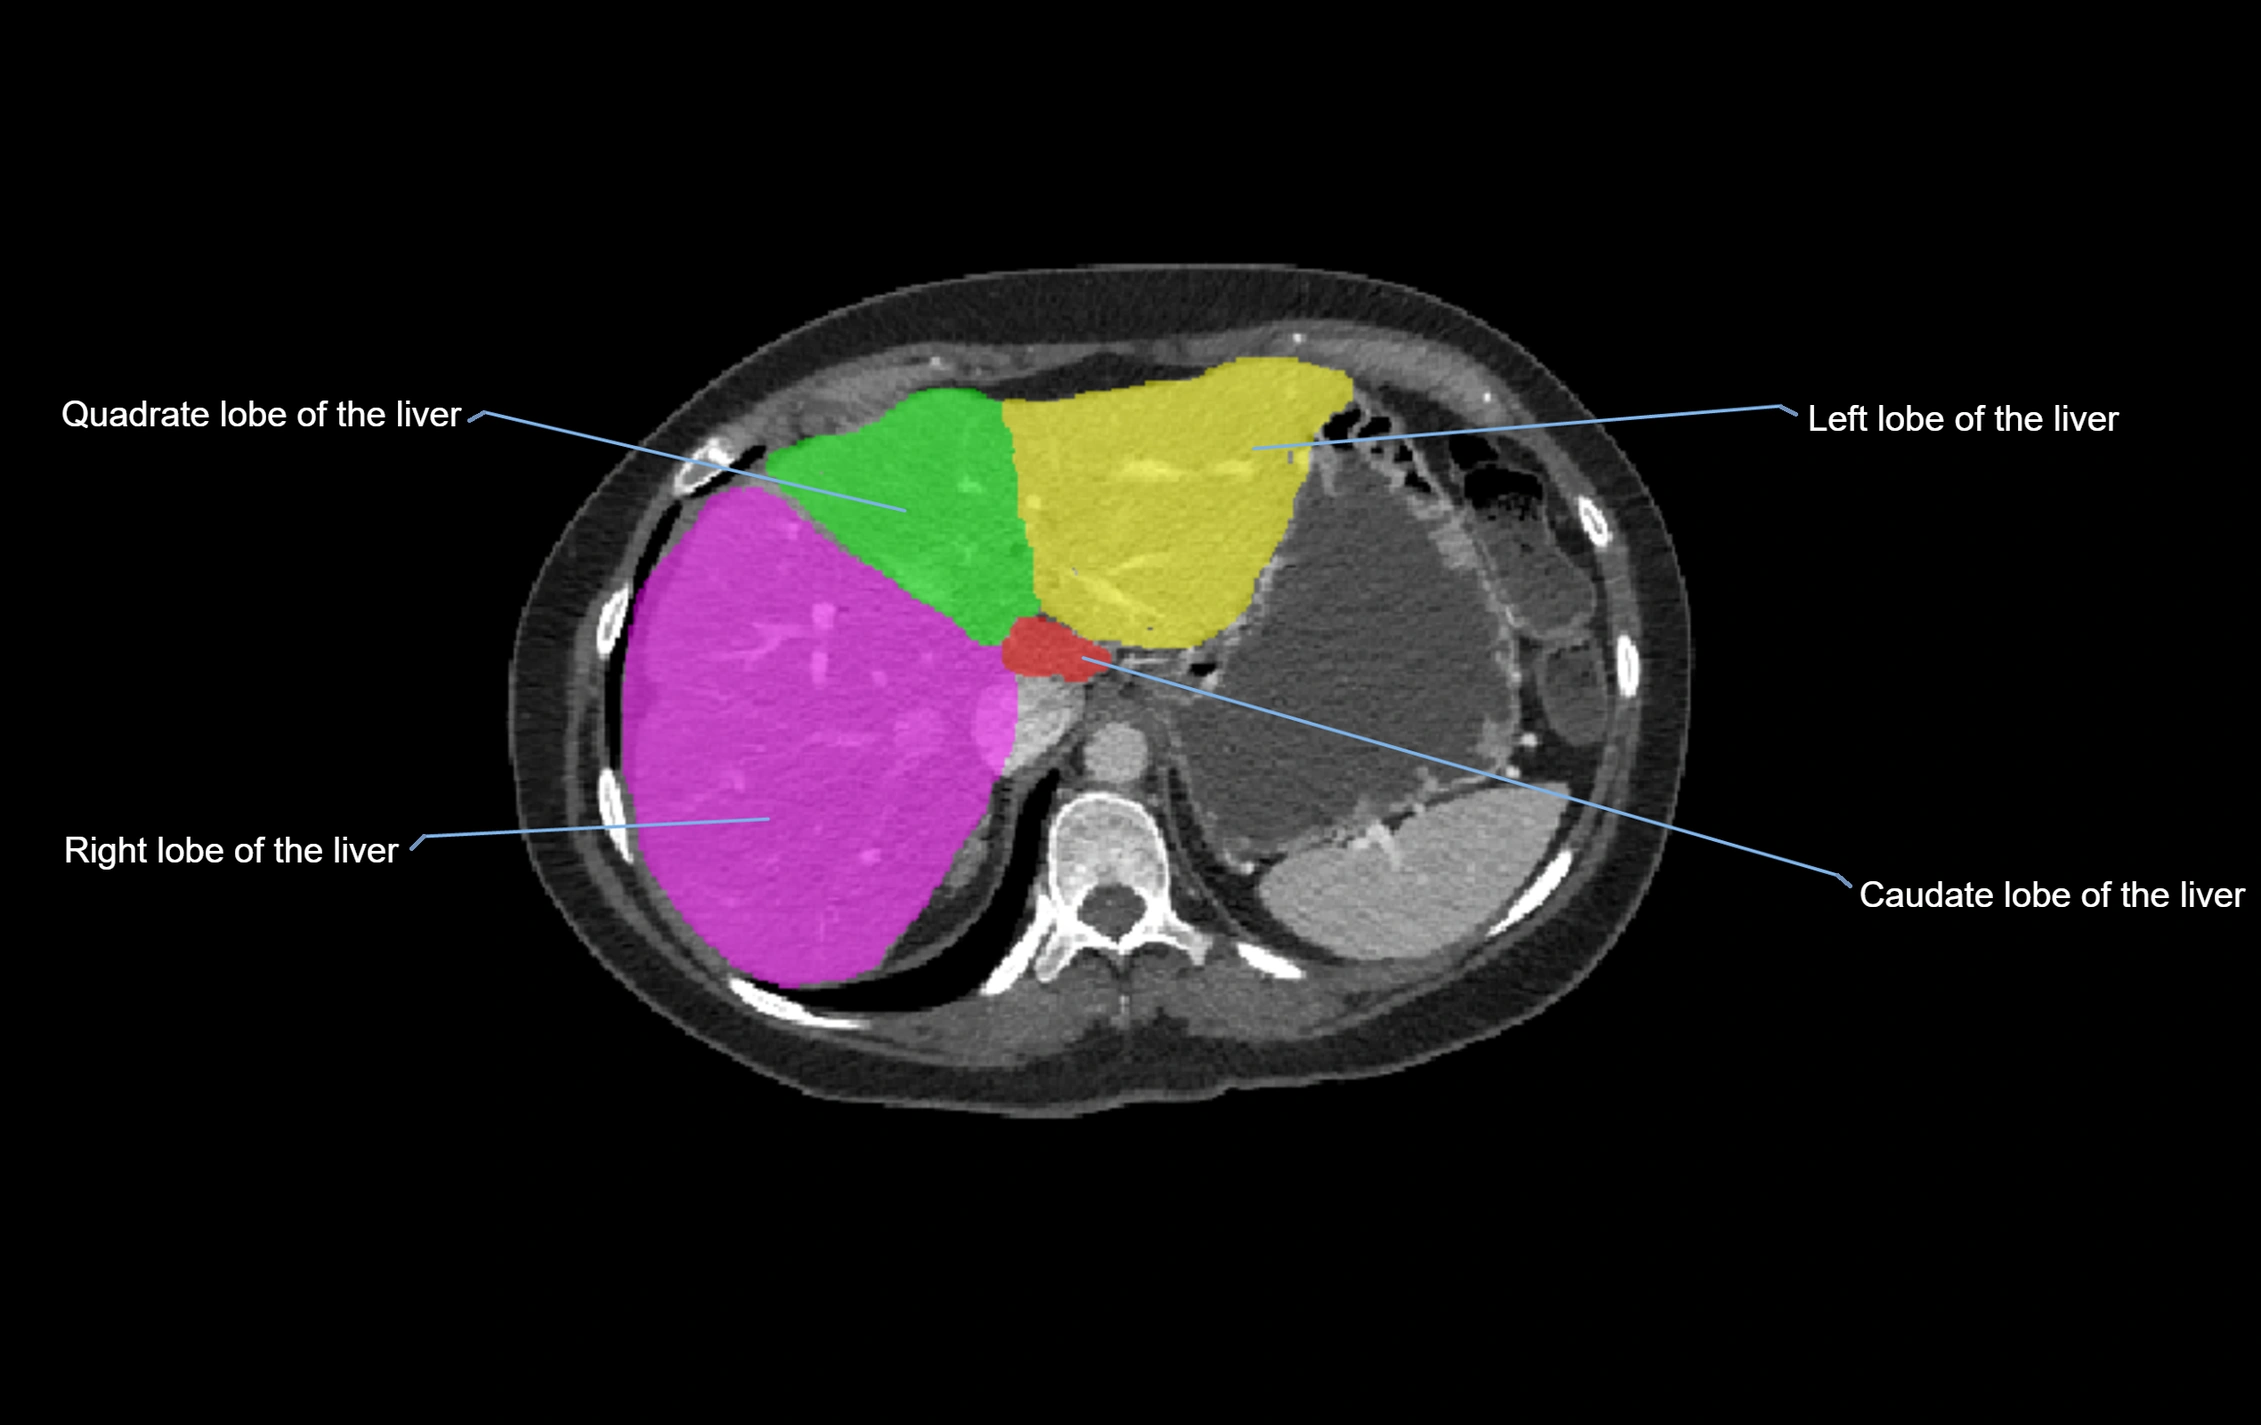

The caudate lobe of the liver is a distinct anatomical subdivision of the liver, designated as segment I in Couinaud’s classification. It lies on the posterior surface of the liver, between the fissure for the ligamentum venosum (left boundary) and the groove for the inferior vena cava (IVC) (right boundary). Superiorly, it is related to the posterior liver surface, and inferiorly it is separated from the left lobe by the porta hepatis.

The caudate lobe is unique because it receives dual portal venous and arterial inflow from both the right and left portal veins and hepatic arteries. It also has independent venous drainage directly into the IVC via multiple small hepatic veins, unlike other lobes that drain through the three main hepatic veins.

This anatomical autonomy makes the caudate lobe especially significant in liver surgery, transplantation, and hepatic venous outflow obstruction syndromes (e.g., Budd–Chiari syndrome). Enlargement of the caudate lobe is a characteristic imaging feature in chronic liver disease and cirrhosis.

CT Appearance

CT Pre-Contrast:

• Caudate lobe appears as a soft-tissue density, isodense to the rest of the liver

• Enlargement may be appreciated in cirrhosis or Budd–Chiari syndrome

CT Post-Contrast:

• Homogeneous enhancement in the portal venous phase, similar to rest of liver

• Independent venous drainage into the IVC may be visualized

• Lesions follow characteristic CT enhancement patterns (HCC: arterial hyperenhancement with washout; hemangiomas: peripheral nodular enhancement with centripetal fill-in)

CT Venous Phase (functional significance):

• Caudate lobe often enhances relatively more than other lobes in Budd–Chiari syndrome, due to preserved venous outflow